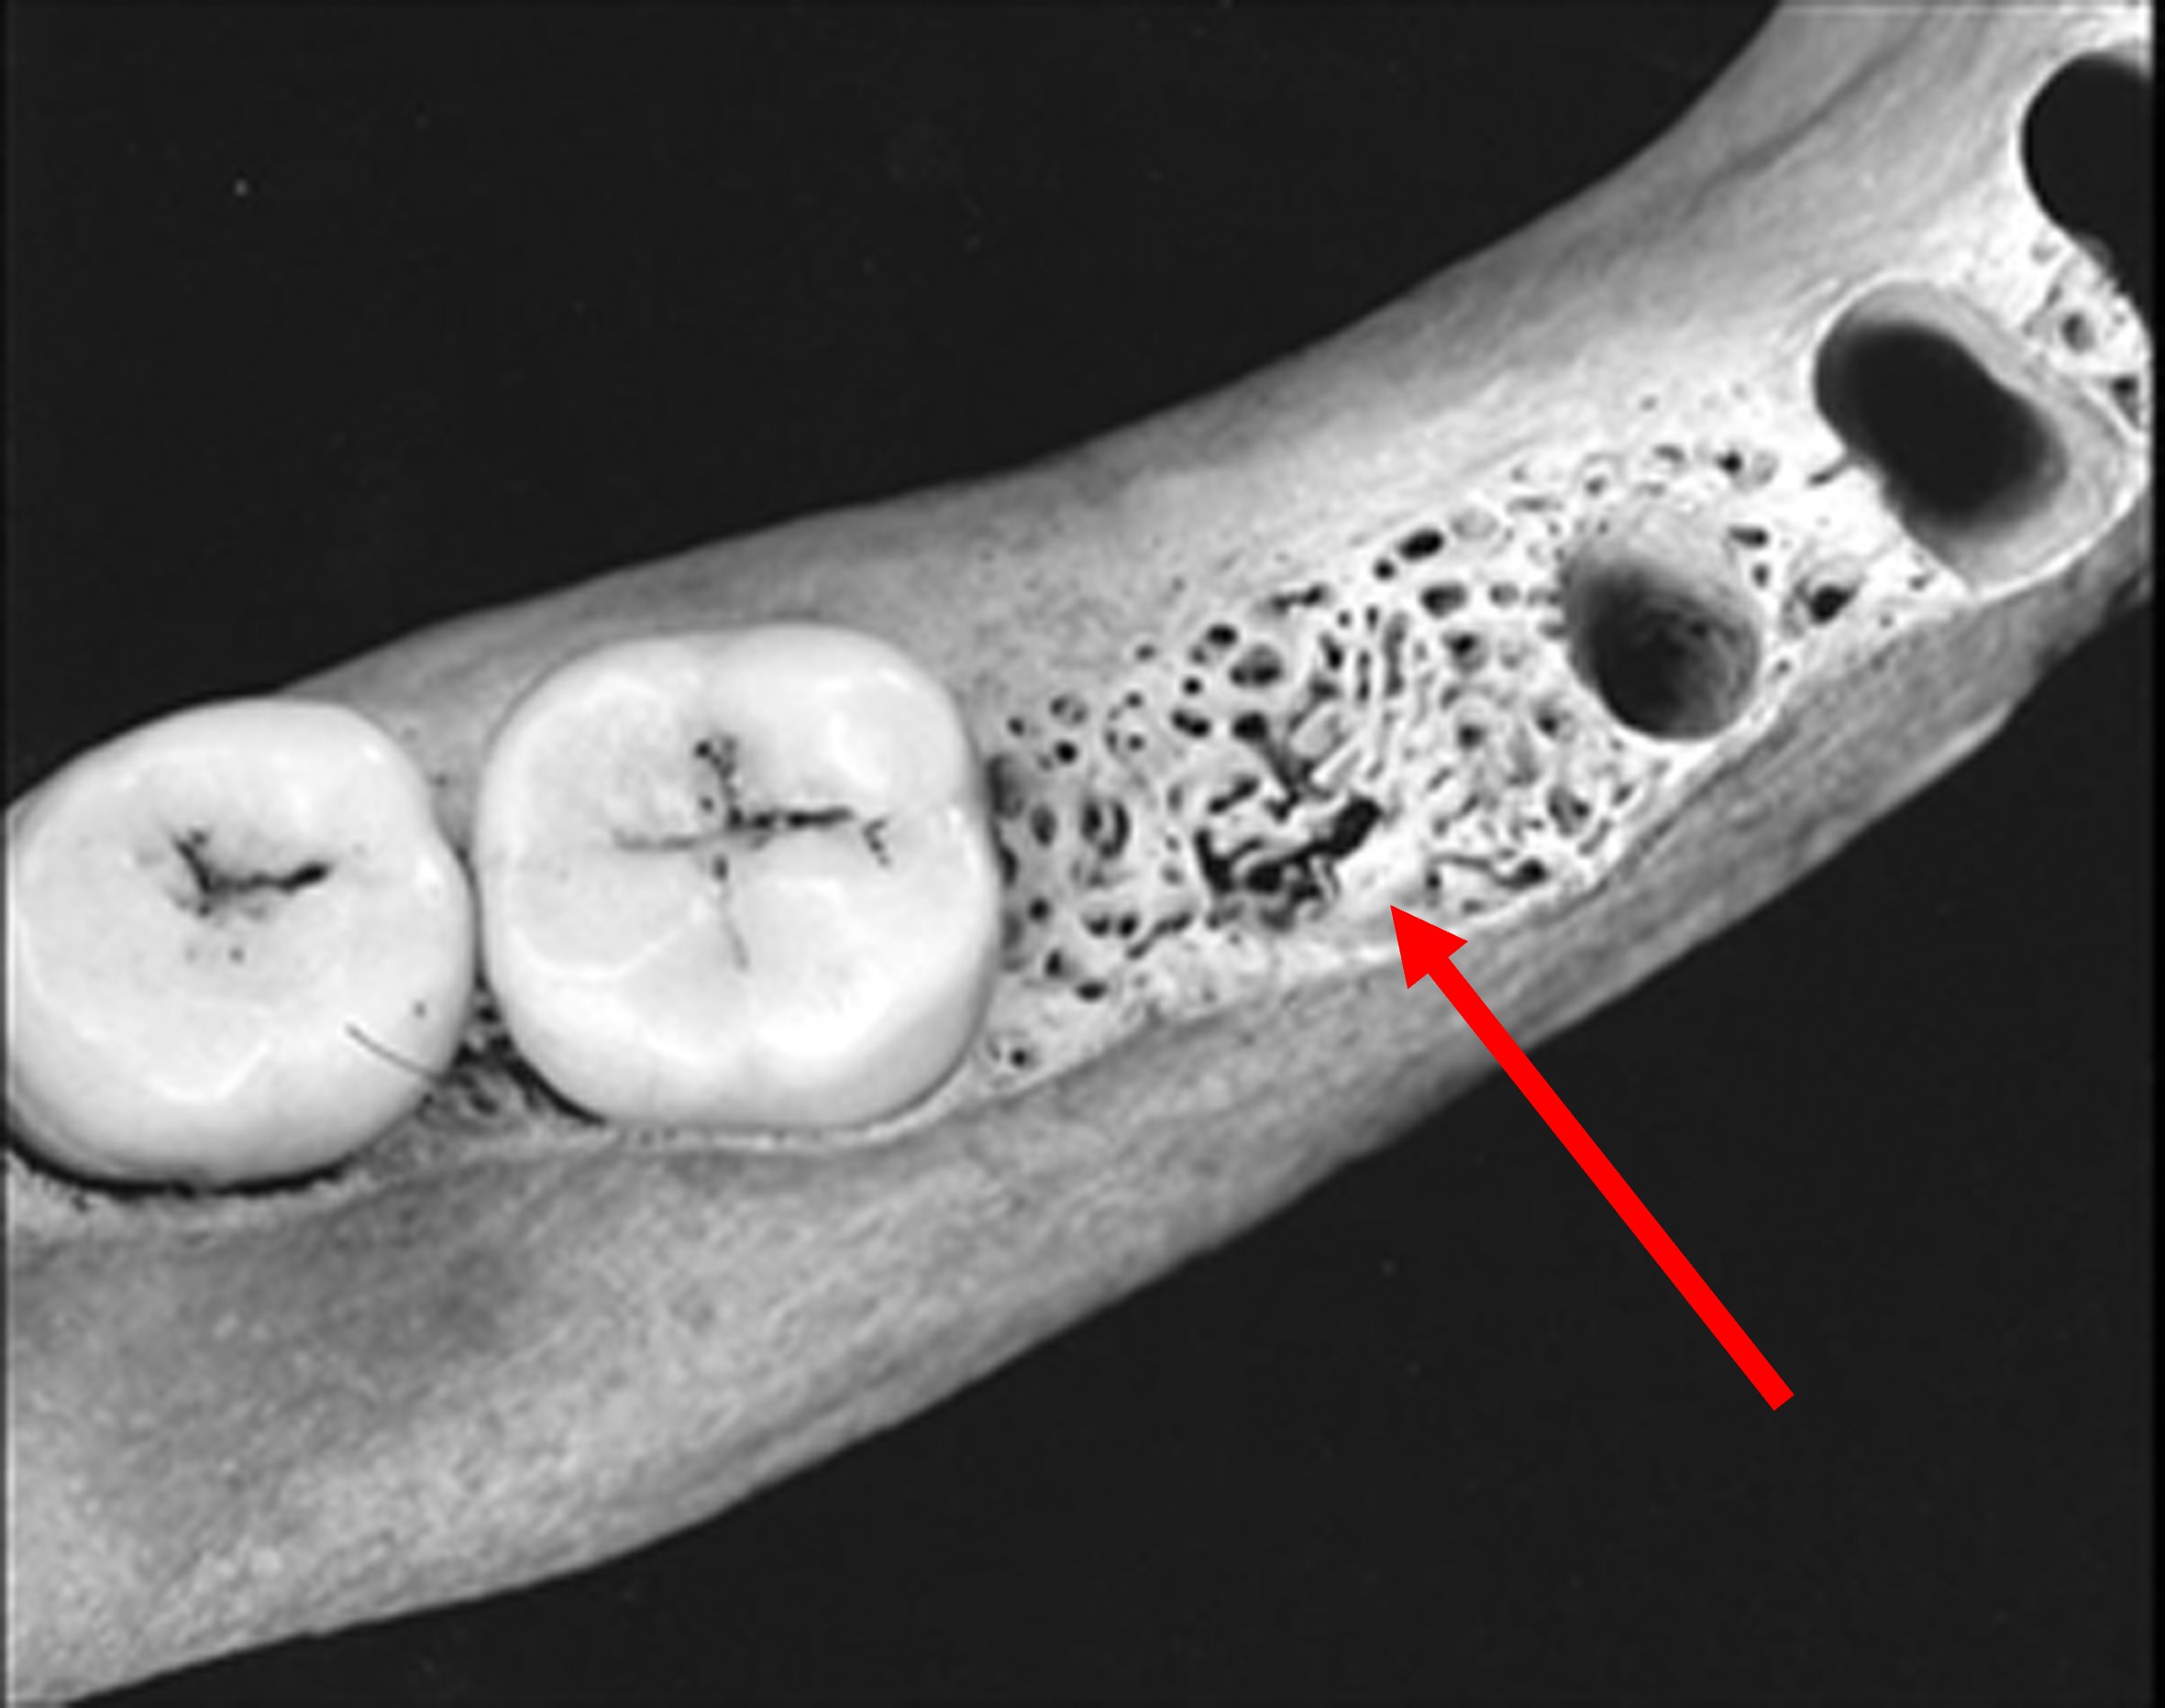

La mandibola di una mummia dell’Età Tolemaica mostra il riempimento di una cavità tra il secondo premolare ed il primo molare destro, probabilmente con del lino impregnato di una qualche resina per proteggere il nervo scoperto